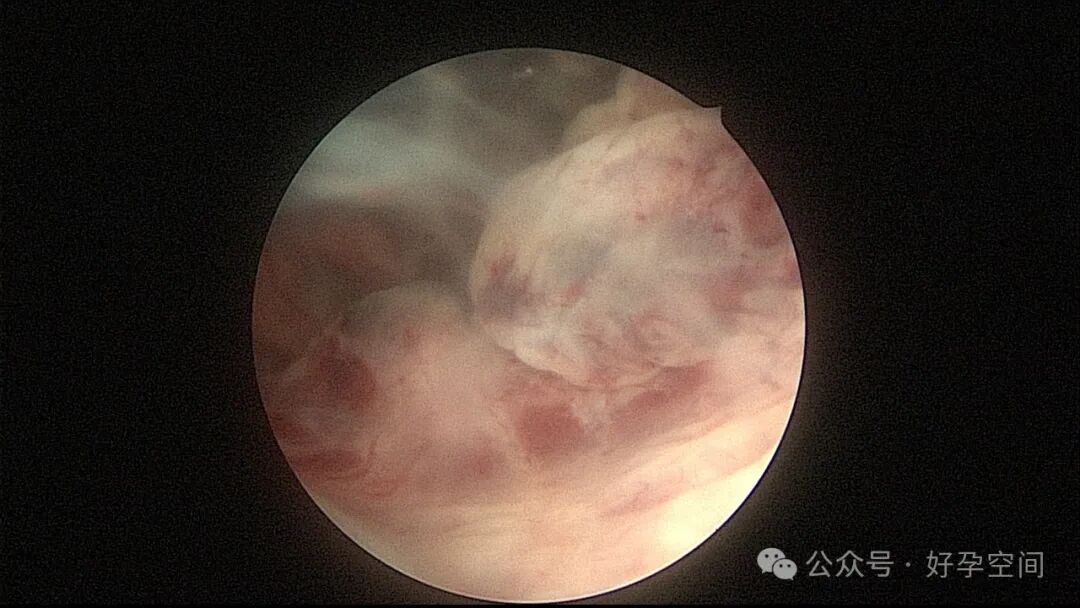

超常胎盘部位(exaggerated placental site,EPS)反应是指在胎盘附着部位组织的过度反应性病变。1991年,WHO将其列入滋养细胞疾病,但目前国内外对该病的诊断尚无统一标准。在正常妊娠中,中间型滋养细胞可侵入底蜕膜或浅肌层,而超常胎盘部位反应时,中间型滋养细胞在胎盘部位大量浸润,并侵入子宫肌层,是正常胎盘反应的加剧,是一种滋养细胞疾病。EPS反应可发生于正常妊娠、流产或葡萄胎后,发生于葡萄胎者浸润力更为明显。EPS以病理诊断为依据,其组织学特征以中间型滋养细胞为主,由子宫内膜向肌层的良性漫润,不破坏原有组织结构,伴有淋巴细胞灶性浸润。EPS是一种非肿瘤性的良性滋养细胞疾病,普通人工流产、宫腔镜取胚或产后出血增多,手术医生主观感觉宫腔已经清理干净,但B超提示宫内占位包块,应考虑到是否存在EPS,建议做宫腔镜探查,切除包块送病检,以明确诊断,避免遗漏其他严重疾病,EPS对症治疗即可,观察病情变化,预后良好。